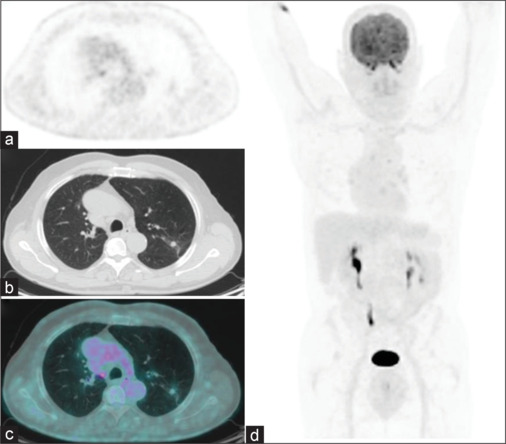

Fetal type adenocarcinoma (FTA) is a rare malignant tumor of the lung that histologically resembles an embryonic lung. Due to its rarity, no studies had investigated the possible role of the 18F-fluorodeoxyglucose positron emission tomography/computed tomography ([18F]FDG PET/CT) in the initial assessment and/or in the restaging of the disease yet. We present a case of a male patient with tongue carcinoma and incidental findings of well-differentiated FTA at [18F]FDG PET/CT. The patient was treated by specific therapy and also performed a subsequent [18F]FDG PET/CT scan that showed a significant reduction of the uptake on lung lesion. This case highlights the potential role and usefulness of PET imaging for staging and posttherapeutic restaging of well-differentiated FTA. The review of the available literature underlined the rarity of the disease since only seven reports were present. Anyway, a possible role of the [18F]FDG PET/CT in the staging of FTA is conceivable.

{"title":"[18F]FDG- PET/CT in Staging and Restaging of Fetal Type Adenocarcinoma of the Lung: A Case Report and a Review of the Literature.","authors":"Pietro Bellini, Francesco Dondi, Gian Luca Viganò, Francesco Bertagna","doi":"10.4103/ijnm.ijnm_113_24","DOIUrl":null,"url":null,"abstract":"<p><p>Fetal type adenocarcinoma (FTA) is a rare malignant tumor of the lung that histologically resembles an embryonic lung. Due to its rarity, no studies had investigated the possible role of the <sup>18</sup>F-fluorodeoxyglucose positron emission tomography/computed tomography ([<sup>18</sup>F]FDG PET/CT) in the initial assessment and/or in the restaging of the disease yet. We present a case of a male patient with tongue carcinoma and incidental findings of well-differentiated FTA at [<sup>18</sup>F]FDG PET/CT. The patient was treated by specific therapy and also performed a subsequent [<sup>18</sup>F]FDG PET/CT scan that showed a significant reduction of the uptake on lung lesion. This case highlights the potential role and usefulness of PET imaging for staging and posttherapeutic restaging of well-differentiated FTA. The review of the available literature underlined the rarity of the disease since only seven reports were present. Anyway, a possible role of the [<sup>18</sup>F]FDG PET/CT in the staging of FTA is conceivable.</p>","PeriodicalId":45830,"journal":{"name":"Indian Journal of Nuclear Medicine","volume":"39 5","pages":"376-380"},"PeriodicalIF":0.5000,"publicationDate":"2024-09-01","publicationTypes":"Journal Article","fieldsOfStudy":null,"isOpenAccess":false,"openAccessPdf":"https://www.ncbi.nlm.nih.gov/pmc/articles/PMC11884344/pdf/","citationCount":"0","resultStr":null,"platform":"Semanticscholar","paperid":null,"PeriodicalName":"Indian Journal of Nuclear Medicine","FirstCategoryId":"1085","ListUrlMain":"https://doi.org/10.4103/ijnm.ijnm_113_24","RegionNum":0,"RegionCategory":null,"ArticlePicture":[],"TitleCN":null,"AbstractTextCN":null,"PMCID":null,"EPubDate":"2025/1/25 0:00:00","PubModel":"Epub","JCR":"Q4","JCRName":"RADIOLOGY, NUCLEAR MEDICINE & MEDICAL IMAGING","Score":null,"Total":0}